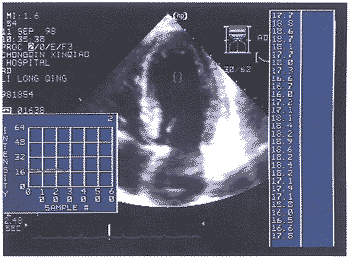

仪器采用美国HP SONOS 5500型超声诊断仪,该机配有完整的AD-IBS联机采样分析软件,含有动态磁光盘记录系统,探头频率为2~4MHz 。常 规检查心脏结构,测量各腔室大小、室壁厚度、心肌重量、二尖瓣血流、左室收缩及舒张功 能参数。在获得标准的乳头肌水平左室短轴和心尖四腔心切面的二维图像后,将仪器调至AD -IBS功能状态,固定仪器设置,包括深度、增益、TGC及LGC,在整个研究过程中保持不变 ,联机采样时固定感兴趣区域的取样框(椭圆形,21×21Pixel),分别置于左室短轴切面的 前壁、前间壁、后间壁、后壁、侧壁、左室腔及四腔切面的二尖瓣环部、室间隔中部(图1) 、左室腔中间(图2)取样,取样跟踪时尽量避开心内、外膜信号的干扰。分析结果包括3项参 数(单位:dB):PPI(峰值-峰值的密度)、AII(平均密度)、SDI(密度标准差)。定量结果可综 合显示在表中(图3),或以坐标图同时显示1~3条定量曲线(图4)。

图2 左室腔血液检测取样及部分结果显示